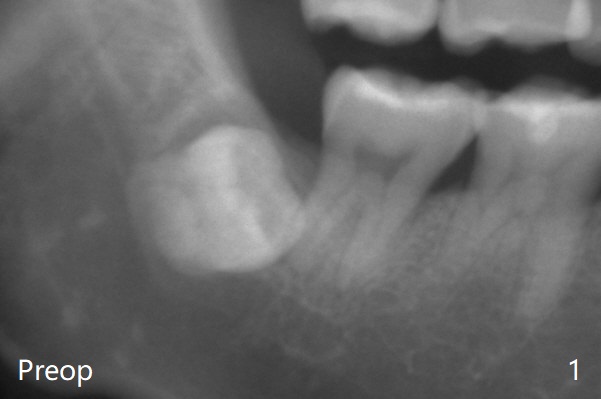

There is bone regeneration at #32 socket 2 years 9 months postop (Fig.3).